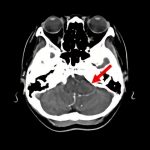

断層撮影